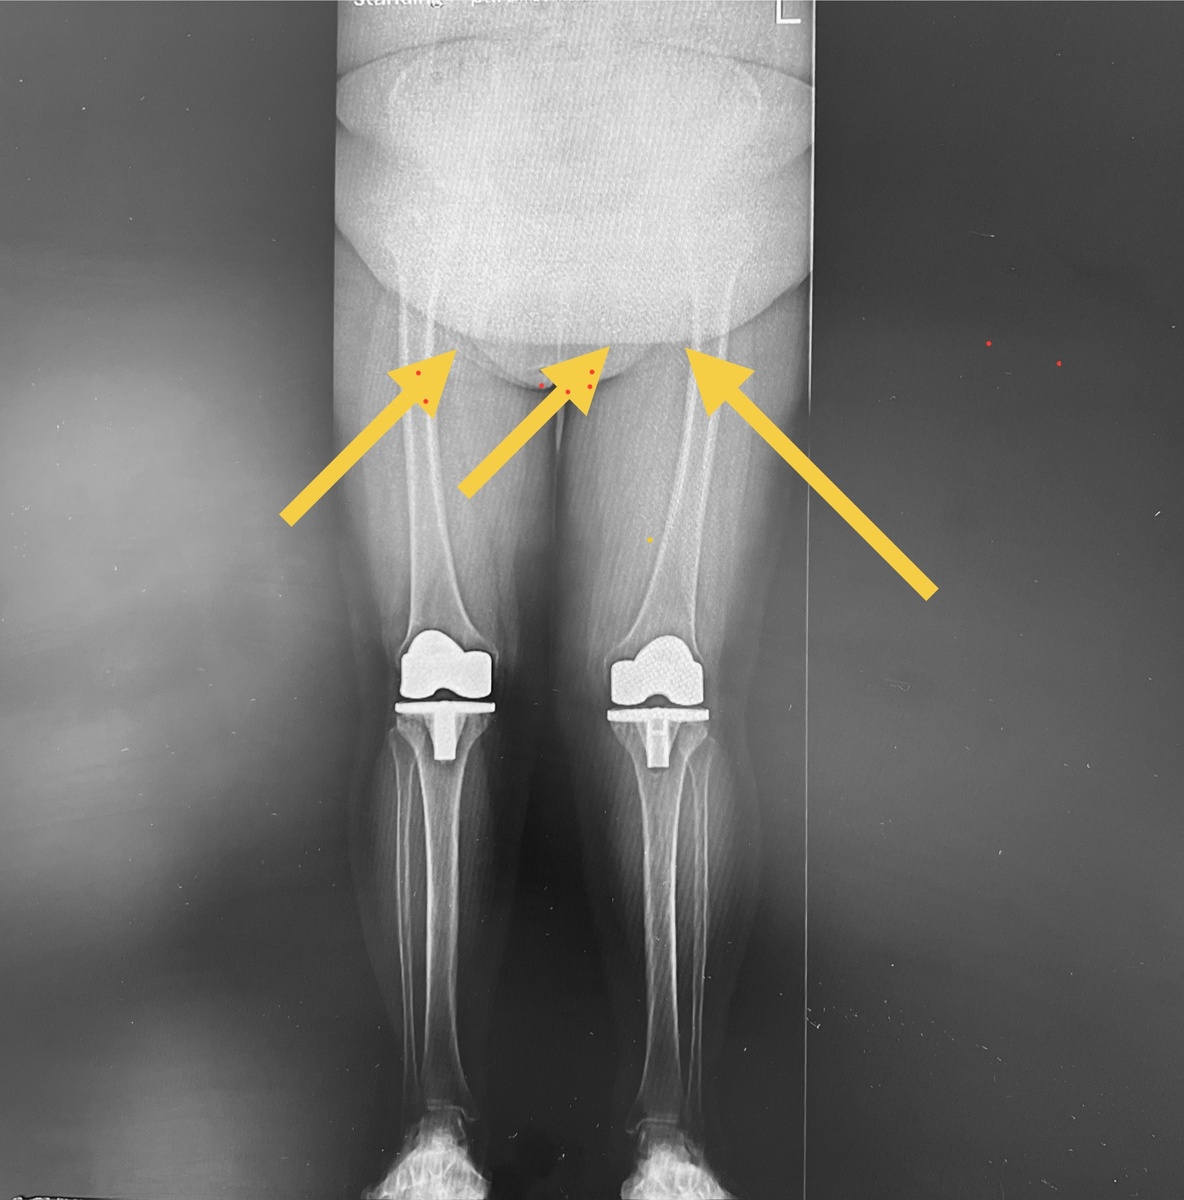

Как на фото. Что показано стрелками? Белое, полукруглое? Живот. Большой тяжелый живот.

Такой живот тянет человека вперед. Чтобы не упасть, человек отклоняется назад, при этом напрягаются мышцы бедер, надколенники сильно прижимаются к бедренным костям - получите боль в переднем отделе суставов. Протезы болят?